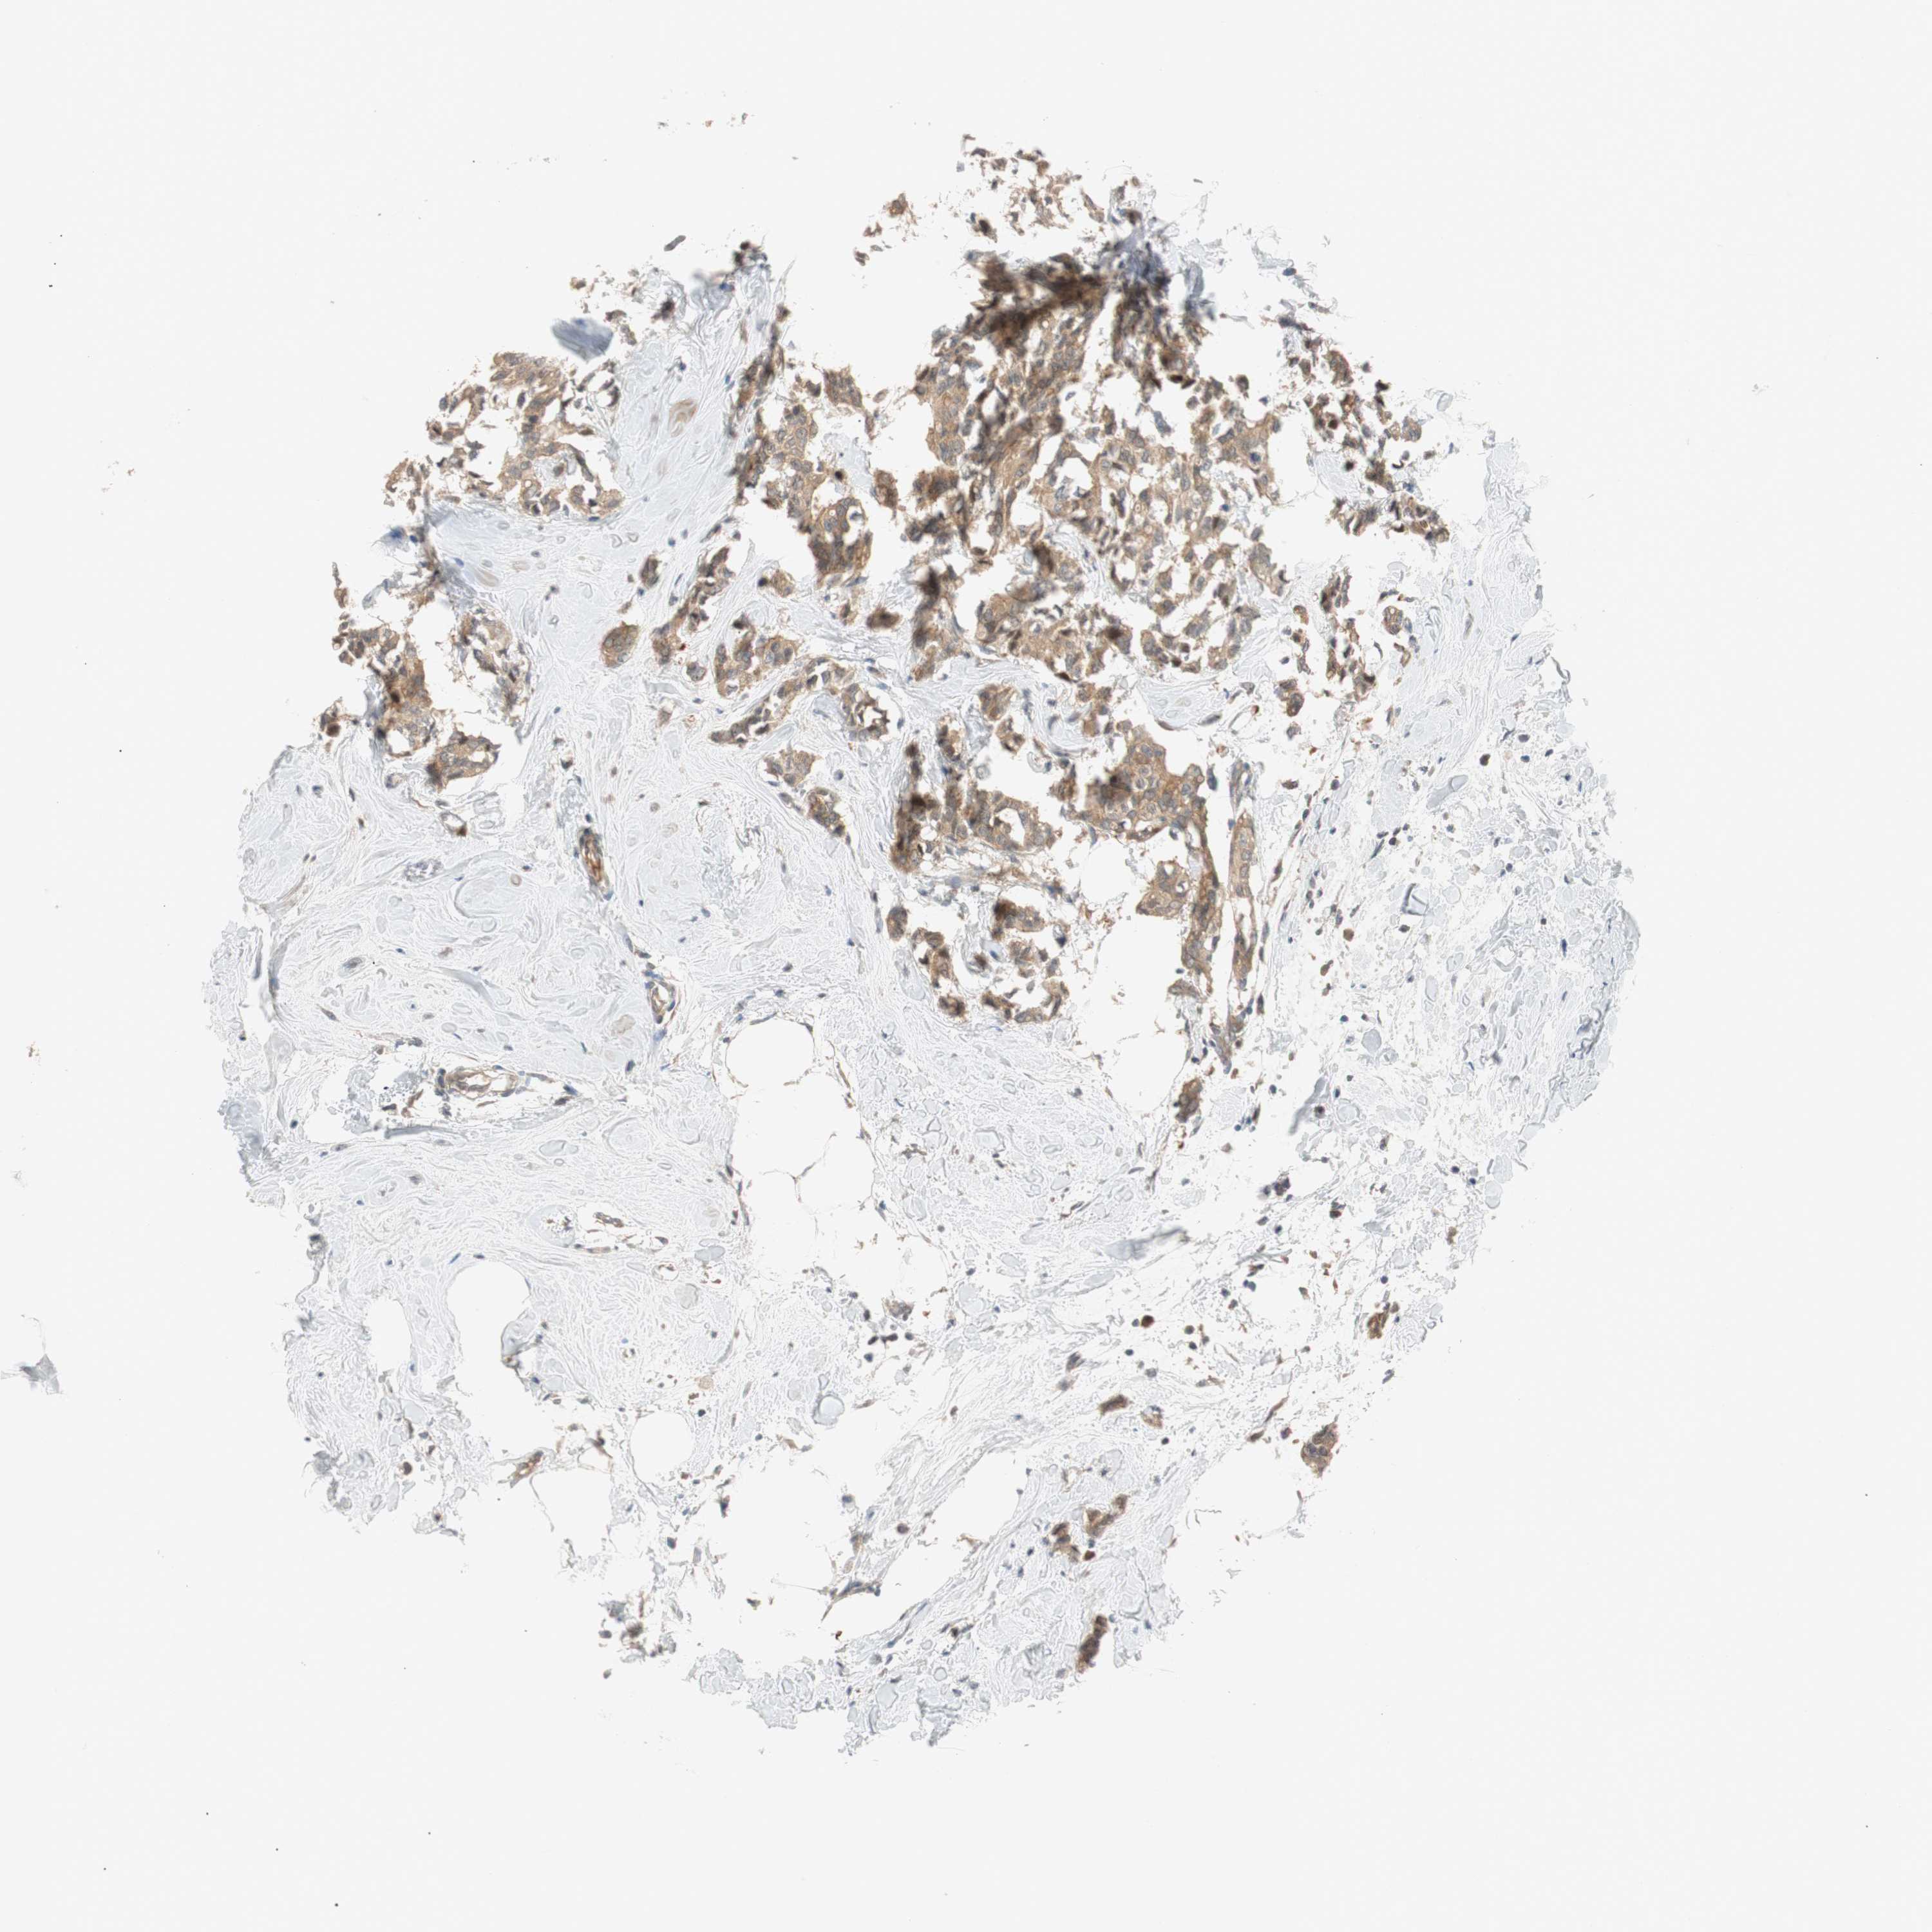

CANCER BREAST CANCER Show tissue menu

BRCA TCGA BRCA VALIDATION PROTEIN EXPRESSION